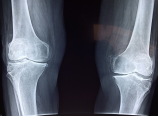

무릎관절의 통증이 오래되어 일상생활이 힘드신 노인분들이 있으신가요?

경제적 이유로 치료를 받지 못하는 노인들의 고통을 경감하고자 무릎 인공관절 지원사업이 진행되고 있습니다. 한쪽 무릎 기준으로 120만원까지 지원된다고 하는데요.

3️⃣ 질환:건강보험급여 ʻ인공관절치환술(슬관절)ʼ 인정기준에 준하는 질환자